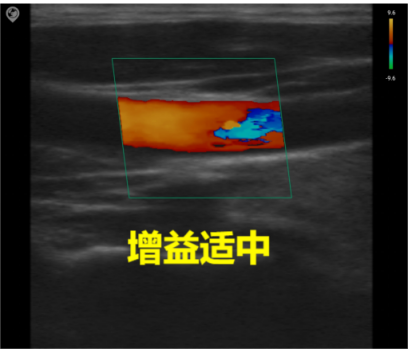

Common parameter adjustment for C mode

Gain

Total gain: Adjusts the sensitivity of blood flow signals, with the gain value displayed in real-time on the image parameter area of the screen.

Image quality: Excessive gain obscures the image with chaotic color spots, while insufficient gain may lead to loss of blood flow signals. During actual adjustment, the optimal setting is to clearly distinguish red and blue blood flow without color aliasing.